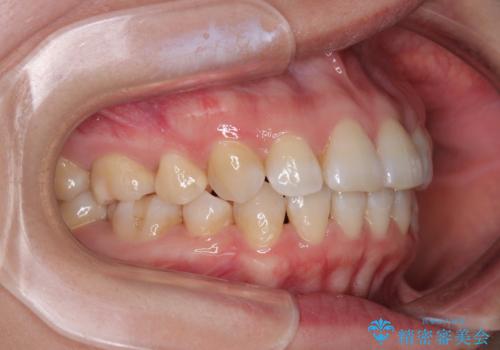

- 上下前歯の後戻りを気にして来院された患者様です。

インビザラインでの治療を希望されていて、デコボコの程度が中等度であり、安価なパッケージにて対応可能と判断されたため、インビザライン・モデレートを用いて矯正治療を行うこととしました。